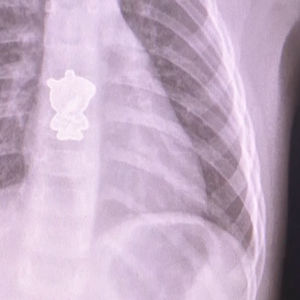

12月24日早上,湖南长沙一岁女童悦悦(化名)起床后一直哭闹不止,家长怎么也找不出原因,于是赶紧将其送往医院检查。医生通过CT检查发现,孩子体内竟藏了个“小猪佩奇”?

孩子母亲回忆,这个小猪佩奇应该是悦悦鞋子上的装饰,鞋子上装饰缝得也不怎么牢固,孩子可能看到好玩,就扣下来了。也不知道什么时候就塞进了嘴里。。。。。。

幸好,检查及时发现了异物,医生已经通过手术,取出了这个让孩子不停哭闹的“元凶”。